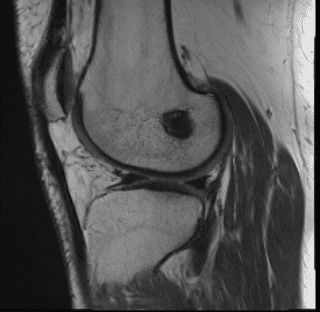

MRI result received, there is status post anterior cruciate ligament reconstruction. The graft is intact. Tubular cyst formation is present within the tibial tunnel. There is a large bucket-handle tear of medial meniscus, displaced into the intercondylar notch and over anterior horn.

There is a tiny capsule remnant posteriorly and peripherally. The lateral meniscus demonstrates free margin fraying of posterior horn and adjacent body aspect without substance tear.